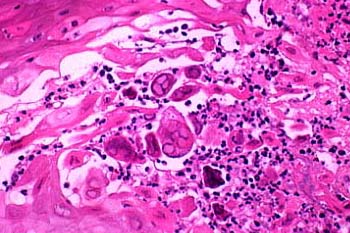

Herpes simplex = العقبول البسيط